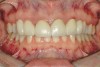

Figure 2a  Corticotomy SFOT. The patient presented with unesthetic anterior bridgework that was placed at age 14 to compensate for congenitally missing Nos. 7 and 10.

Figure 2a

Figure 2d  Prerestorative orthodontics was completed in 5 months. Final result 3 years, 4 months after completion.

Figure 2d

Figure 2e  Teeth Nos. 5 and 12 were converted to Nos. 6 and 11, and Nos. 6 and 11 were converted to Nos. 7 and 10. Nos. 4 and 13 were enlarged. Note stability and absence of orthodontic relapse. Before-and-after smiles.

Figure 2e

Figure 2f  Teeth Nos. 5 and 12 were converted to Nos. 6 and 11, and Nos. 6 and 11 were converted to Nos. 7 and 10. Nos. 4 and 13 were enlarged. Note stability and absence of orthodontic relapse. Before-and-after smiles.

Figure 2f